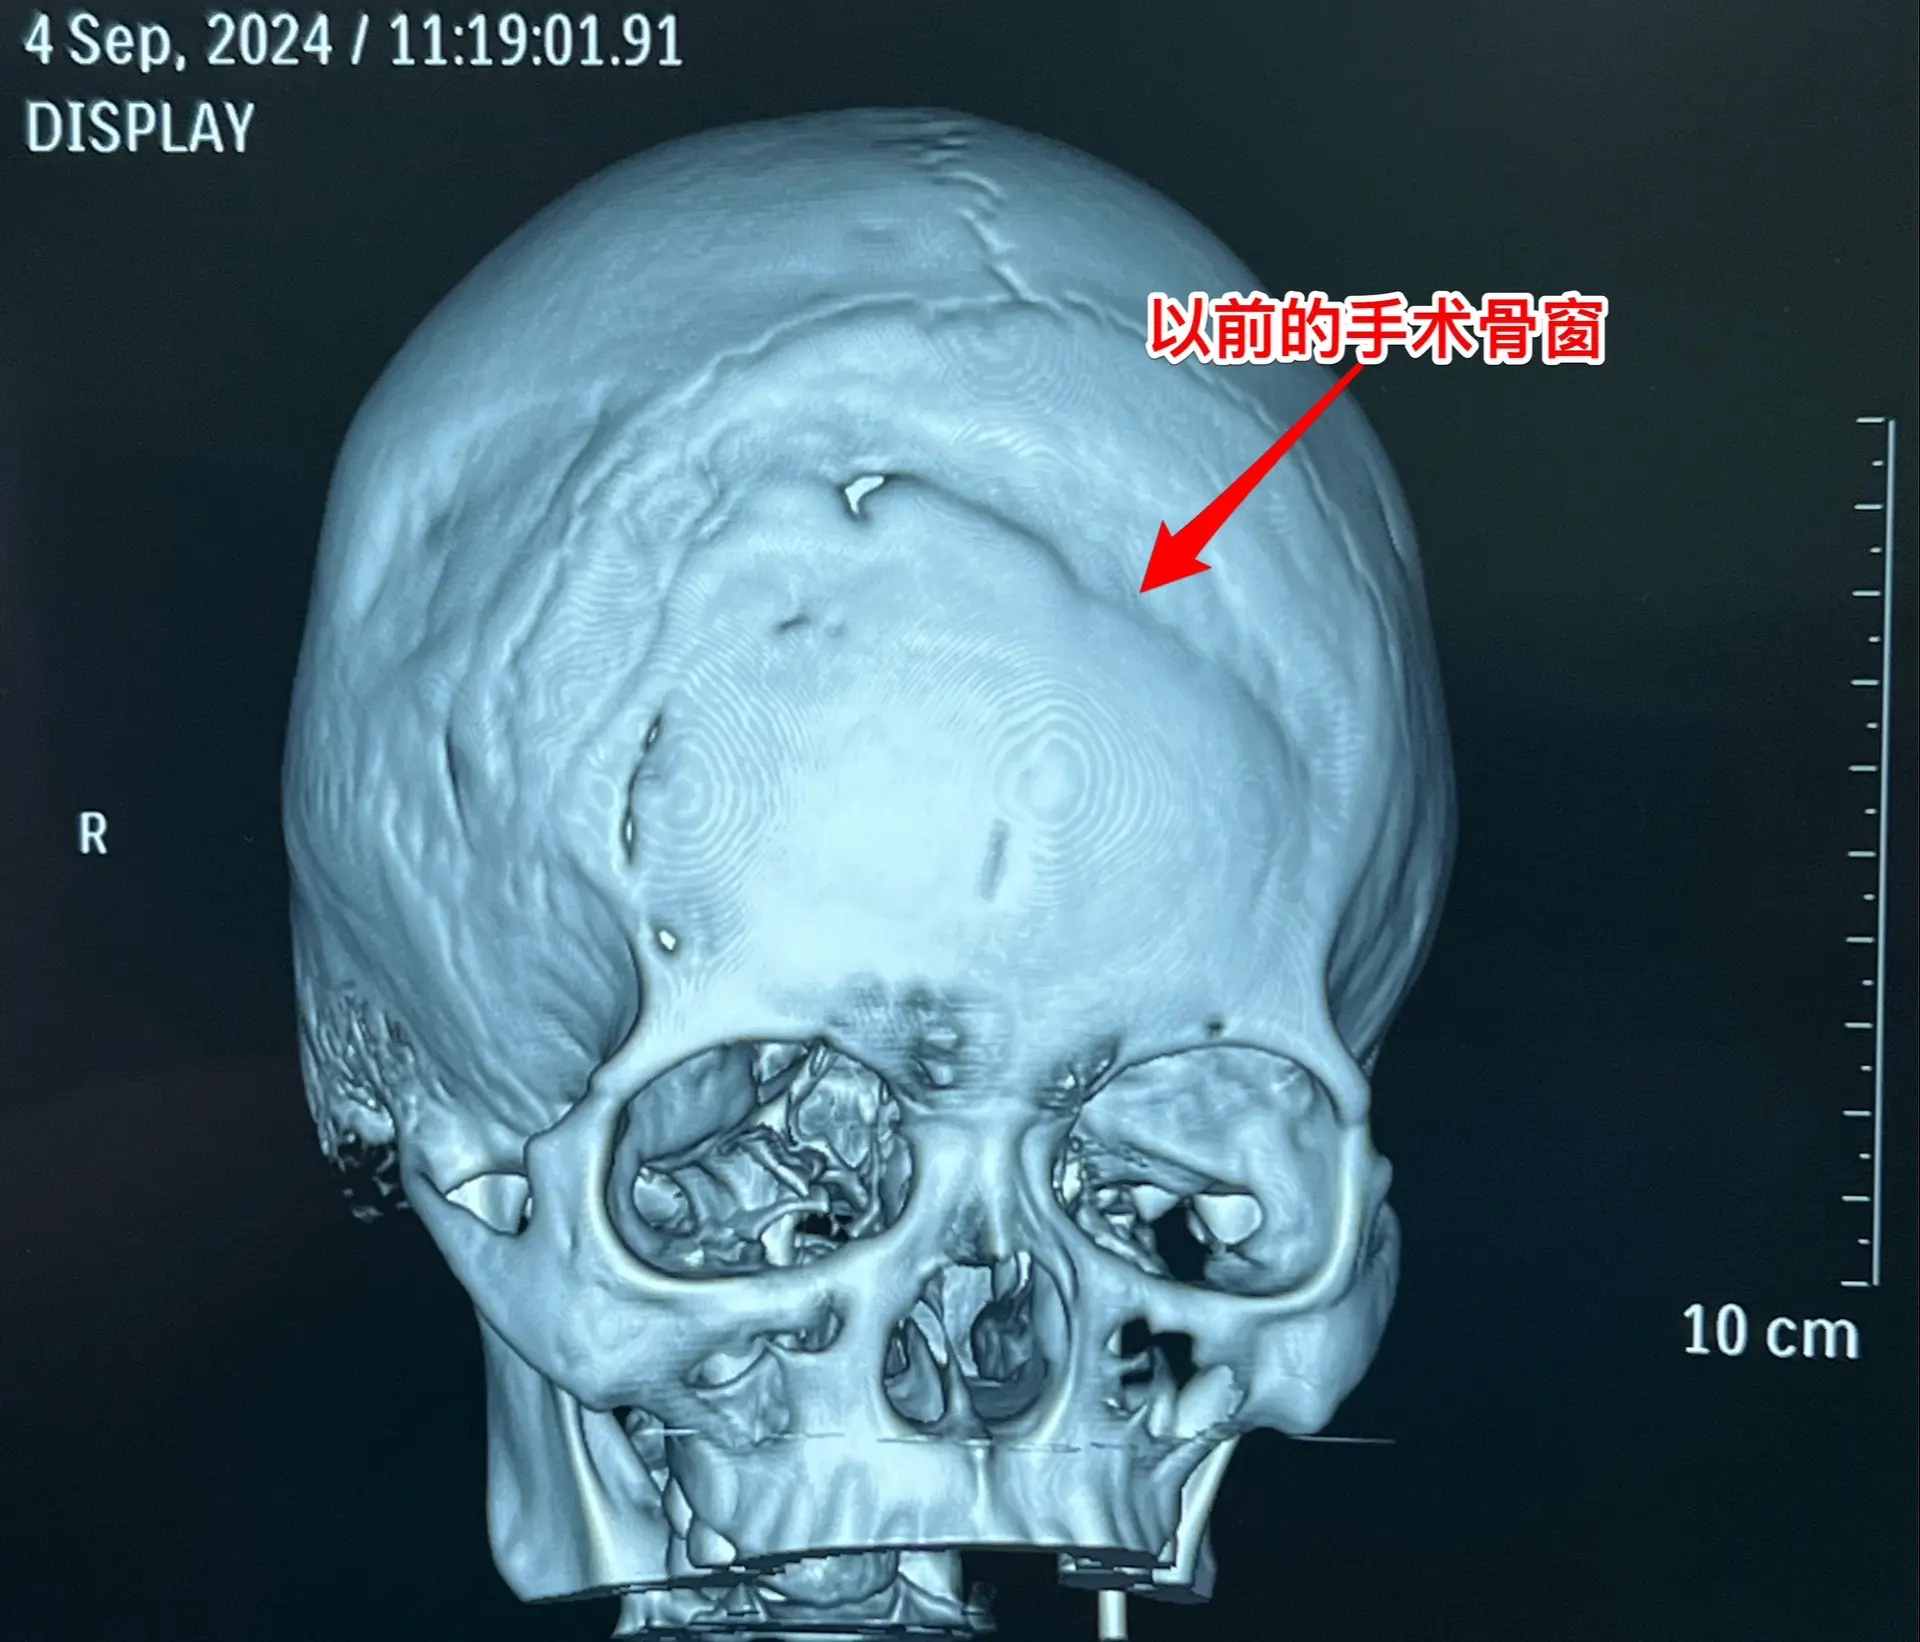

9月11日作了手术,经纵裂入路顺利切除肿瘤。经过仔细对比之前的磁共振,找到了复发肿瘤的起源点,才确定了这个手术入路。手术后患者语言、运动能力均好。发热持续时间比较长,经用抗菌药治疗后平稳了,十一前出院了。